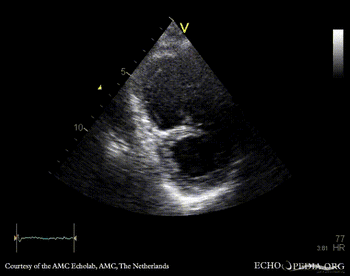

PLAX: enlarged right ventricle in patient with carcinoid PSAX: enlarged right ventricle in patient with carcinoid, diastolic flattening of IAS